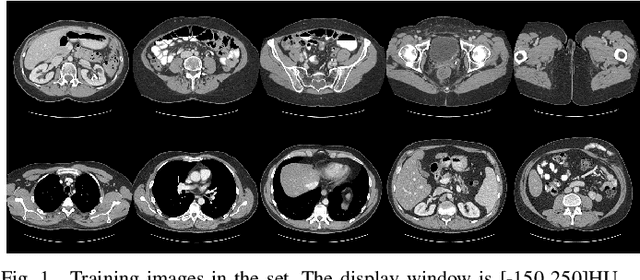

Abstract:Accurate medical image segmentation demands the integration of multi-scale information, spanning from local features to global dependencies. However, it is challenging for existing methods to model long-range global information, where convolutional neural networks (CNNs) are constrained by their local receptive fields, and vision transformers (ViTs) suffer from high quadratic complexity of their attention mechanism. Recently, Mamba-based models have gained great attention for their impressive ability in long sequence modeling. Several studies have demonstrated that these models can outperform popular vision models in various tasks, offering higher accuracy, lower memory consumption, and less computational burden. However, existing Mamba-based models are mostly trained from scratch and do not explore the power of pretraining, which has been proven to be quite effective for data-efficient medical image analysis. This paper introduces a novel Mamba-based model, Swin-UMamba, designed specifically for medical image segmentation tasks, leveraging the advantages of ImageNet-based pretraining. Our experimental results reveal the vital role of ImageNet-based training in enhancing the performance of Mamba-based models. Swin-UMamba demonstrates superior performance with a large margin compared to CNNs, ViTs, and latest Mamba-based models. Notably, on AbdomenMRI, Encoscopy, and Microscopy datasets, Swin-UMamba outperforms its closest counterpart U-Mamba by an average score of 3.58%. The code and models of Swin-UMamba are publicly available at: https://github.com/JiarunLiu/Swin-UMamba